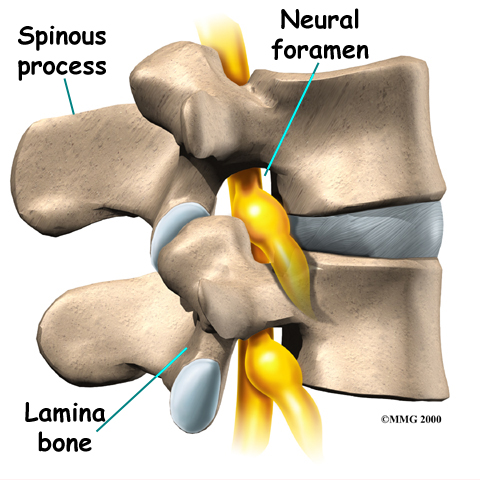

Surgeons perform this procedure through an incision in the low back. The incision reaches to the , the bony projections off the back of the vertebrae. The surgeon must move aside the muscles along the spine, called the paraspinal muscles. The fusion itself involves the lamina bone, the protective roof over the back surface of the spinal cord. In some cases, the surgeon may enlarge the neural foramina, the tunnels where the nerve roots leave the spinal cord.

The spinal nerves are also affected by too much vertebral motion. They begin to rub where they pass through the neural foramina and become swollen and irritated. Also, the neural foramina narrow when a vertebra slides too far forward or backward over the vertebra below. This immediately where they pass through the neural foramina. Nerve swelling, irritation, and pinching produce neurogenic pain. This type of pain often radiates down one or both legs below the knee. Fusion stops this harm to the nerves.

The surgeon first removes any pressure from nearby nerves. This may involve removing part or all of the lamina bone. (The lamina forms the back portion of the bony ring covering the spinal canal.) Then the surgeon takes out any disc fragments and scrapes off nearby bone spurs. In this way, the nerves inside the spinal canal are relieved of additional tension and pressure. The nerve roots are checked to see if they move freely in the spinal canal and as they leave the spine through the small holes between the vertebrae, the neural foramina. If not, the surgeon may cut a larger opening in the neural foramina. This procedure is called foraminotomy.